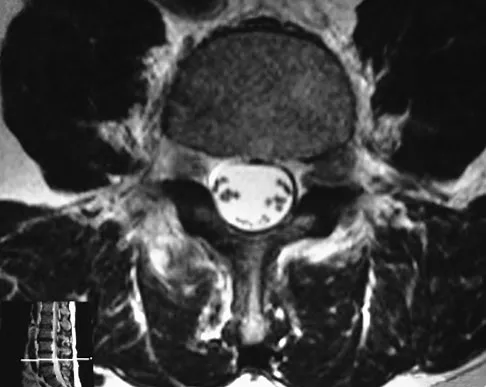

An otherwise healthy 45-year-old woman reports the onset of severe right leg pain. Figure 20a shows an axial MRI scan of the L4-5 level, and Figure 20b shows a sagittal view with the arrow at the L4-5 level. What nerve root is the most likely source of her pain?

Explanation